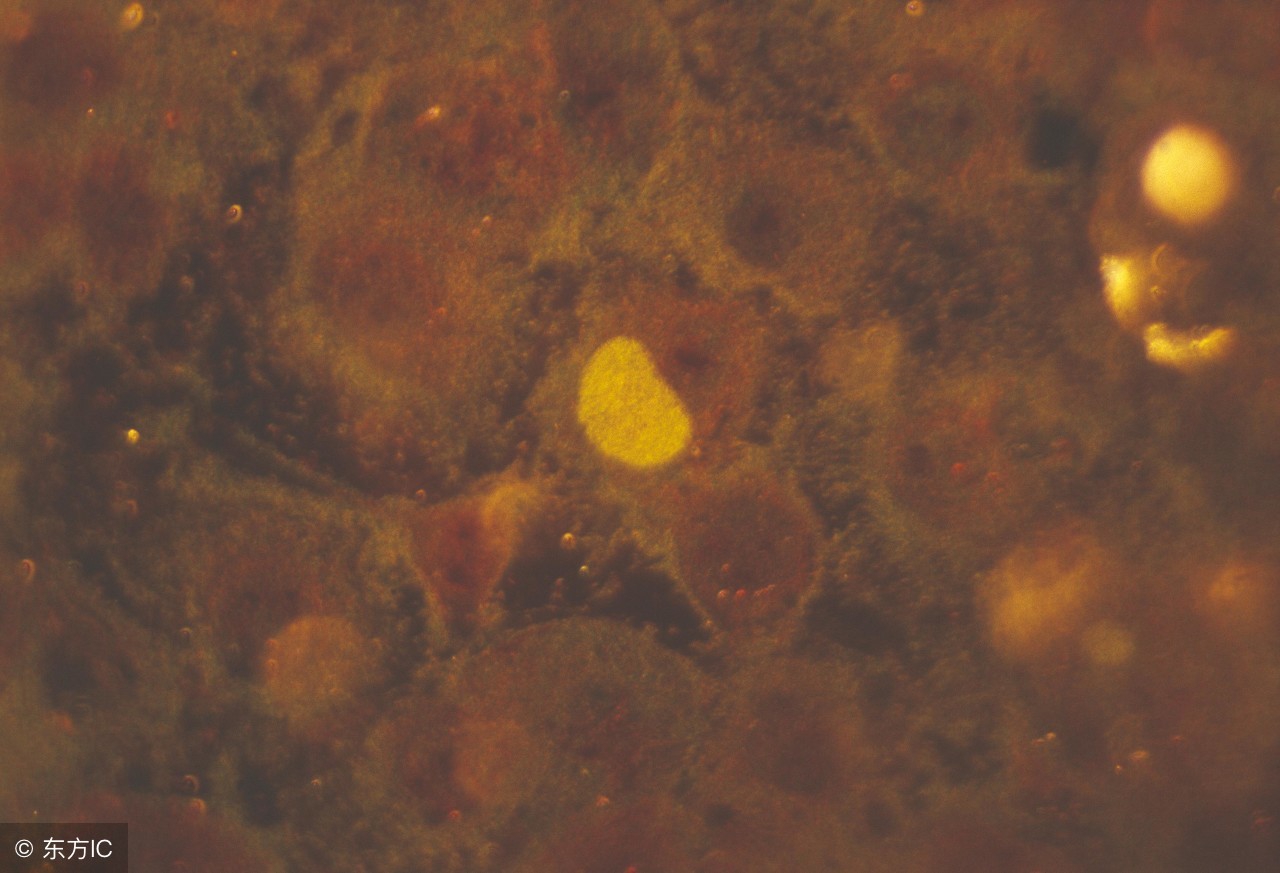

女性宫颈炎的主要症状是白带增多。急性宫颈炎白带呈脓性,伴下腹及腰骶部坠痛,或有尿频、尿急、尿痛等膀胱刺激征。慢性宫颈炎白带呈乳白色黏液状,或淡黄色脓性……那么宫颈炎治疗前后注意什么呢?下面我们来简单了解一下。

宫颈炎与宫颈FK1关系密切。有关防FK1普查资料显示,宫颈无糜烂者有0.39%患宫颈FK1,而患子宫糜烂者却有2.05%患宫颈FK1。说明积极治疗慢性宫颈炎,并针对采取积极的预防措施,对保障女性健康及防治宫颈FK1有重大意义。